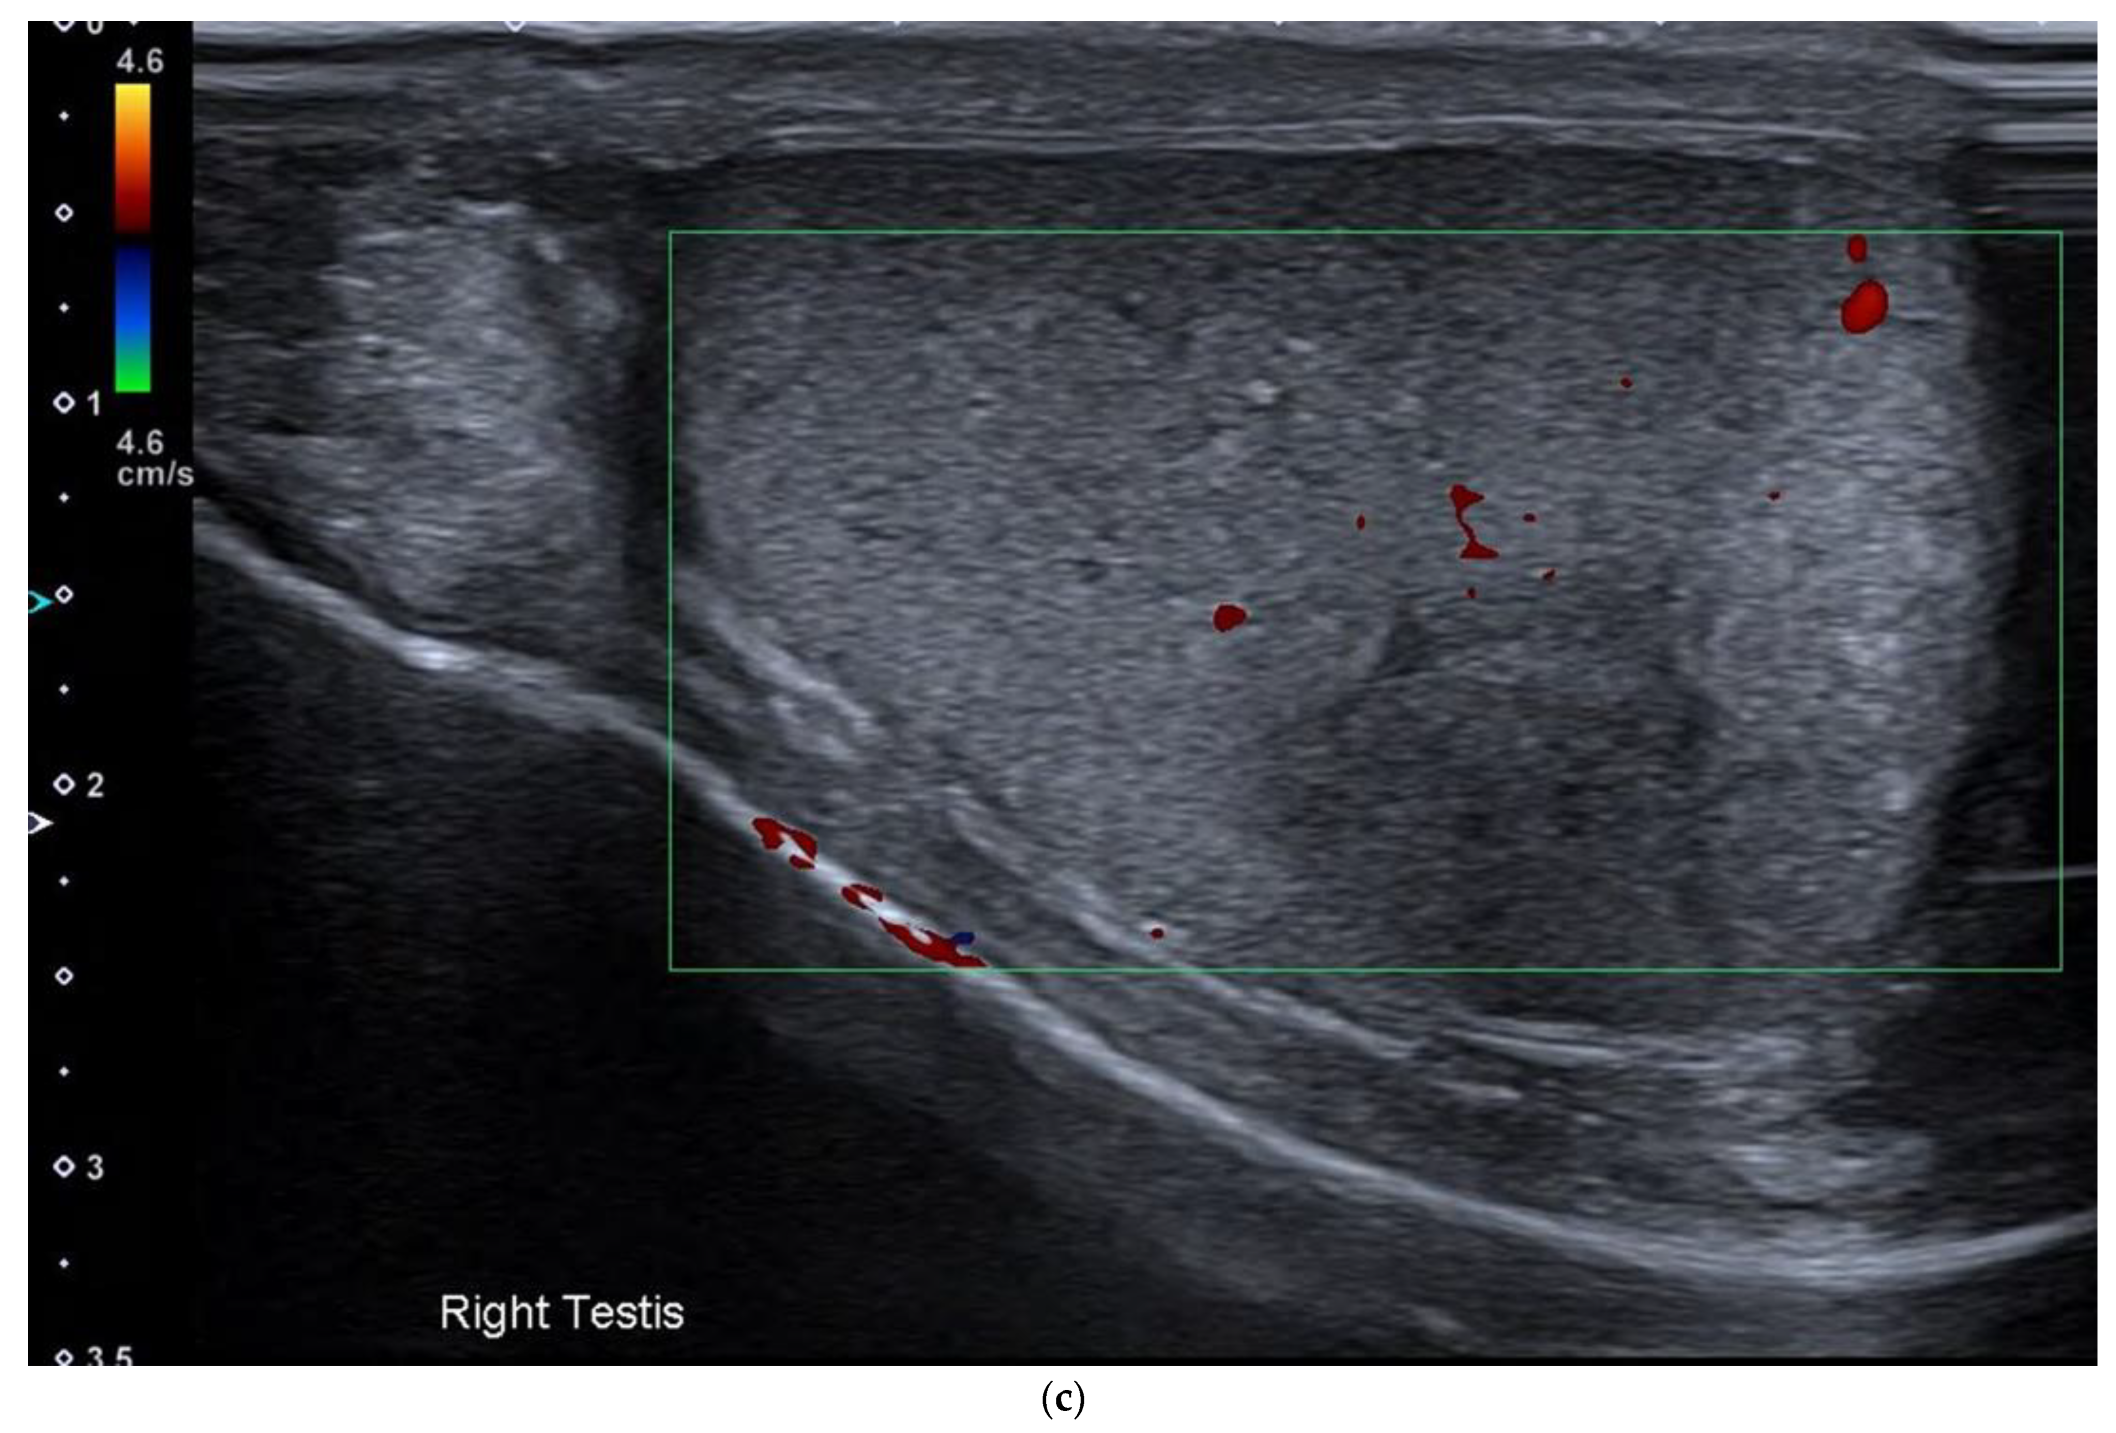

4.1. Seminomatous Germ Cell Tumour

| Seminomas | Homogenous and hypoechoic Well circumscribed Occasionally contain cystic components or calcifications |